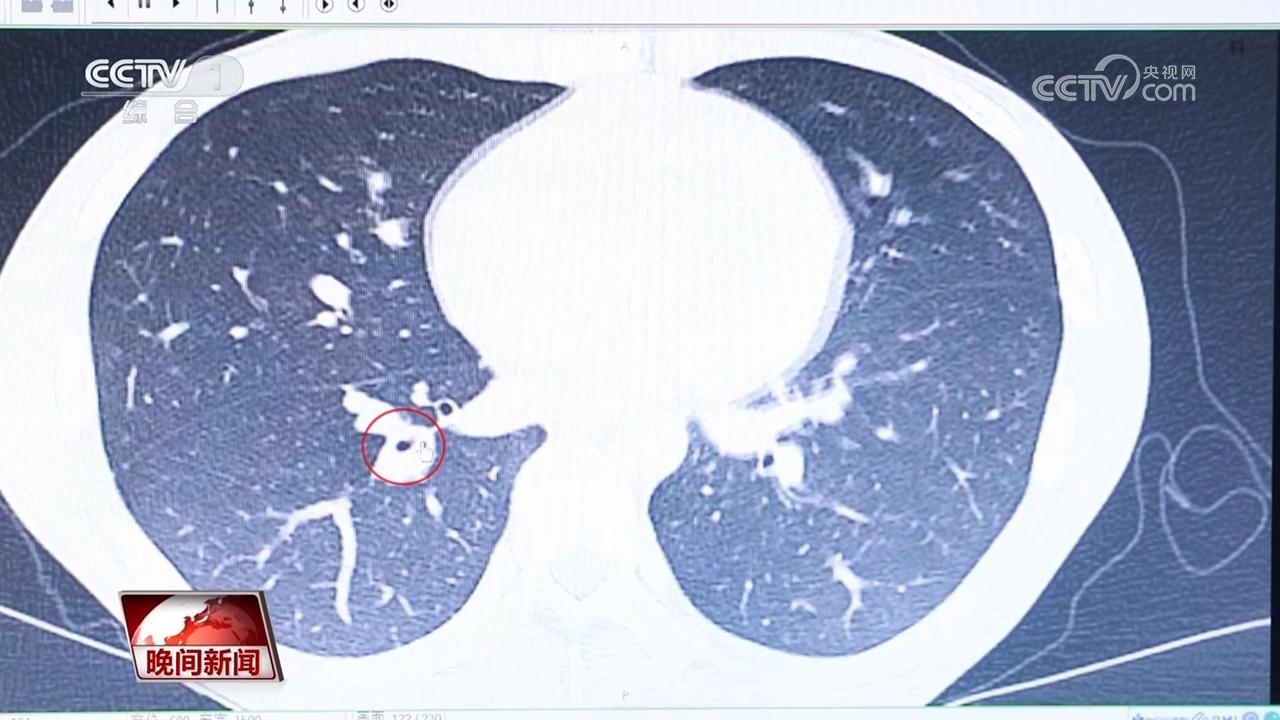

檢查發現,小楊右肺下方的氣管里,藏著一個小小的異物。專家們認為這就是小楊一年來反復發熱、咳嗽的病因。

首都醫科大學附屬北京世紀壇醫院 呼吸與危重癥醫學科主任 錢進:異物在氣道時間比較長,會形成纖維組織的包裹。容易造成氣道的阻塞,造成的氣道的一個炎癥,在這個炎癥背景下,異物反倒不容易發現了。